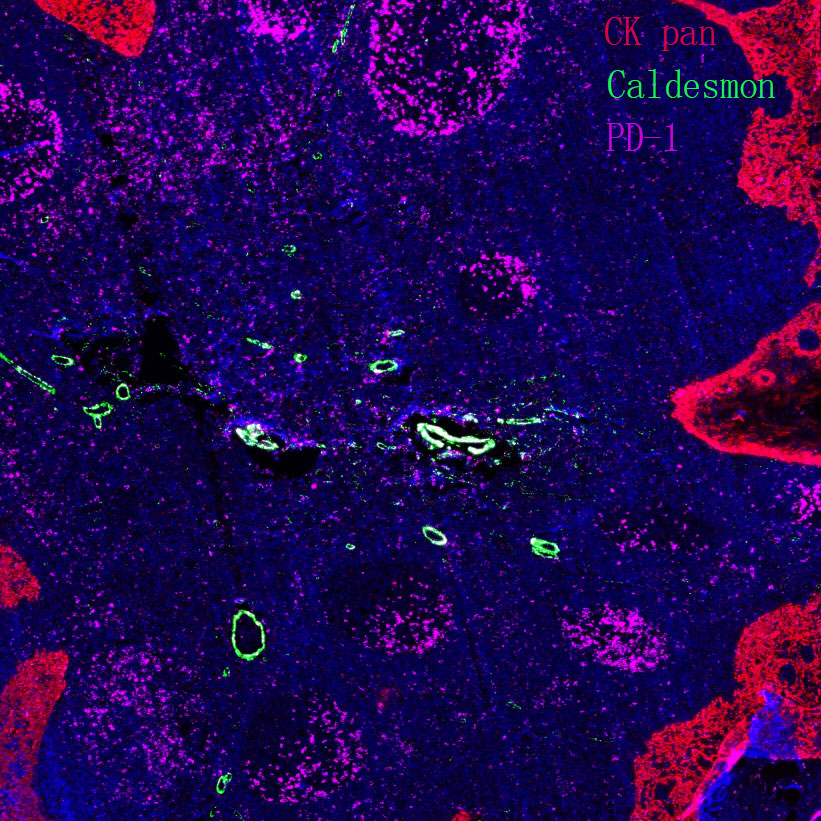

Explore Our Recommended Popular Products

More products

Primary Antibodies, Secondary Antibodies, mIHC Kits, ELISA Kits, Proteins, Molecular Biology Products,Cell Lines,Reagents ...